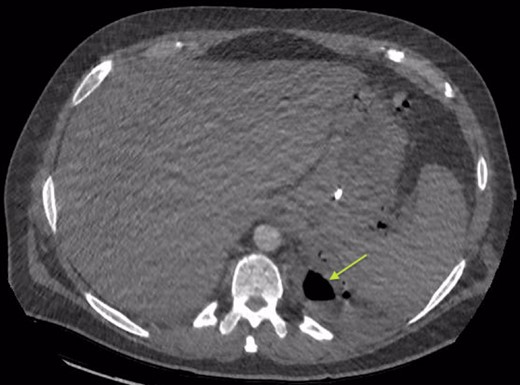

Chest X-ray in ICU following drainage showed what was thought to be Pneumomediastinum (Figs 1 and 2), and given this concern he was referred to the Cardiothoracic service. Subsequent CT suggested a large loculated hydro-pneumothorax, which in retrospect represented the drained Pseudocyst communicating through the diaphragm (Figs 3 and 4).

Area of communication between the drained Pseudocyst and the Left Pleura. Space noted with arrow.

An Intercostal drain was inserted under CT-guidance aiming to decompress the pleural space. Amylase level in the pleural drainage was 880 U/l, Lipase 472 U/l. There was significant reduction of the Hydropneumothorax (Fig. 5). Given his young age, potential for loss of lung volume and infection he proceeded to decortication.